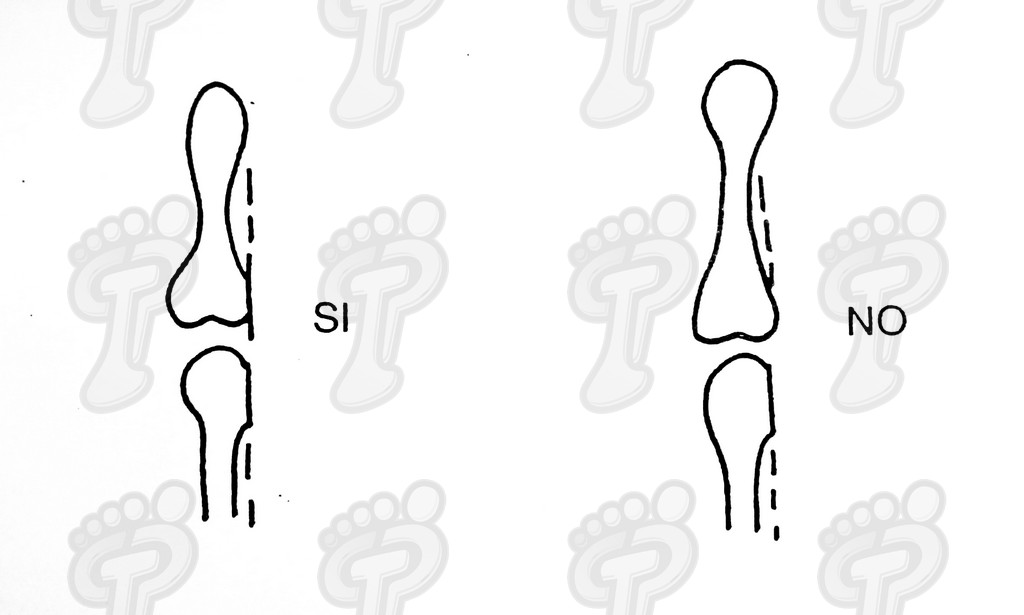

Se realiza la técnica mediante anestesia troncular y sin hemostasia (o al menos, tras el legrado). Hacemos una incisión transversal en la zona dorsoplantar distal a dos o tres milímetros de la prominencia ósea, se introduce el bisturí perpendicularmente al eje de la falange hasta tocar hueso, y a partir de ahí, se desciende bien próximo al tejido ósea para separar partes blandas y delimitar la exóstosis. No se debe incidir lateralmente porque podríamos dañar el paquete neurovascular. Se introduce un cincel separando tejido óseo blando y se delimita la prominencia ósea, la cual suele ser mayor que en la radiografía debido a una zona cartilaginosa radiotransparente. Se legra exhaustivamente con la lima de proximal a distal y de profundidad a superficie (sin vaivén). En las primeras capas (cortical y periostio) notamos que la lima patina y a continuación percibimos el raspado óseo. Con el pulgar de la mano pasiva presionamos de proximal a distal para que salgan al exterior las partículas óseas legradas. Legramos ampliamente ya que al producir un traumatismo óseo siempre hay una regeneración ósea debida a la rica red capilar superficial. Si no lo hacemos así, se puede volver a regenerar el tejido óseo produciendo de nuevo y en poco tiempo la exóstosis. Favorecemos el sangrado de la zona para ayudar a eliminar posibles partículas óseas. Lavamos abundantemente la incisión con suero fisiológico. Volvemos a realizar otra radiografía dorsoplantar intraquirúrgica, a ser posible en la misma posición pre-quirúrgica (la radiografía oblícua no da imagen real del tamaño de exóstosis y la lateral no muestra nada). Hemos de observar en la radiografía que la cabeza de la falange proximal está en el mismo plano que la base de la falange media, ya que si no puede producir algias post-operatorias. Si observamos una nebulosa en la radiografía, son pequeñas partículas o fragmentos óseos que deben drenarse mediante lavados ya que si no se reagrupan y vuelven a regenerar la exóstosis de nuevo. Se han de hacer lavados y radiografías hasta quedar la zona totalmente limpia de fragmentos óseos. Infiltramos anestésico y corticoides en proporción 9 a 1. No hemos de abusar del corticoide porque al entrar en contacto con la trabécula ósea que hemos dejado como capa externa, puede producir problemas graves post-operatorios, tales como la osteoporosis. Se aconseja primero cargar el corticoide y luego el anestésico para evitar que se cristalice el corticoide produciendo trastornos yatrogénicos. Una vez infiltrada la mezcla, presionamos la herida proximal a distal para drenarla ya que sólo nos interesa el efecto farmacológico antiinflamatorio. A continuación, suturamos con seda 5/0 mediante dos puntos simples. En el caso que os mostramos ferulizamos el quinto dedo con una gasa de “U”, impidiendo así la movilización dorsoplantar y, para más sujeción, se une al cuarto dedo con la ayuda de un vendaje circular. Puede impregnarse en yodo la férula en forma de “U” para darle mayor rigidez o consistencia y por lo tanto, menor movilidad al quinto dedo. El vendaje debe ser semicompresivo alineado el dedo. Aconsejamos al paciente reposo durante 48 horas. Pautamos la analgesia correspondiente, y le informamos de las actuaciones que debe efectuar ante determinadas anomalías. Retiramos el apósito quirúrgico a las 48 horas y se cura con povidona yodada dos veces al día (mañana y tarde). Enseñamos al paciente a hacer el vendaje en forma de “U”. A los siete días retiramos la sutura y confeccionamos una cresta de silicona, que debería emplear hasta alcanzar la normalidad articular. Dicha silicona ha de ser utilizada durante un período que oscile entre seis meses a un año.